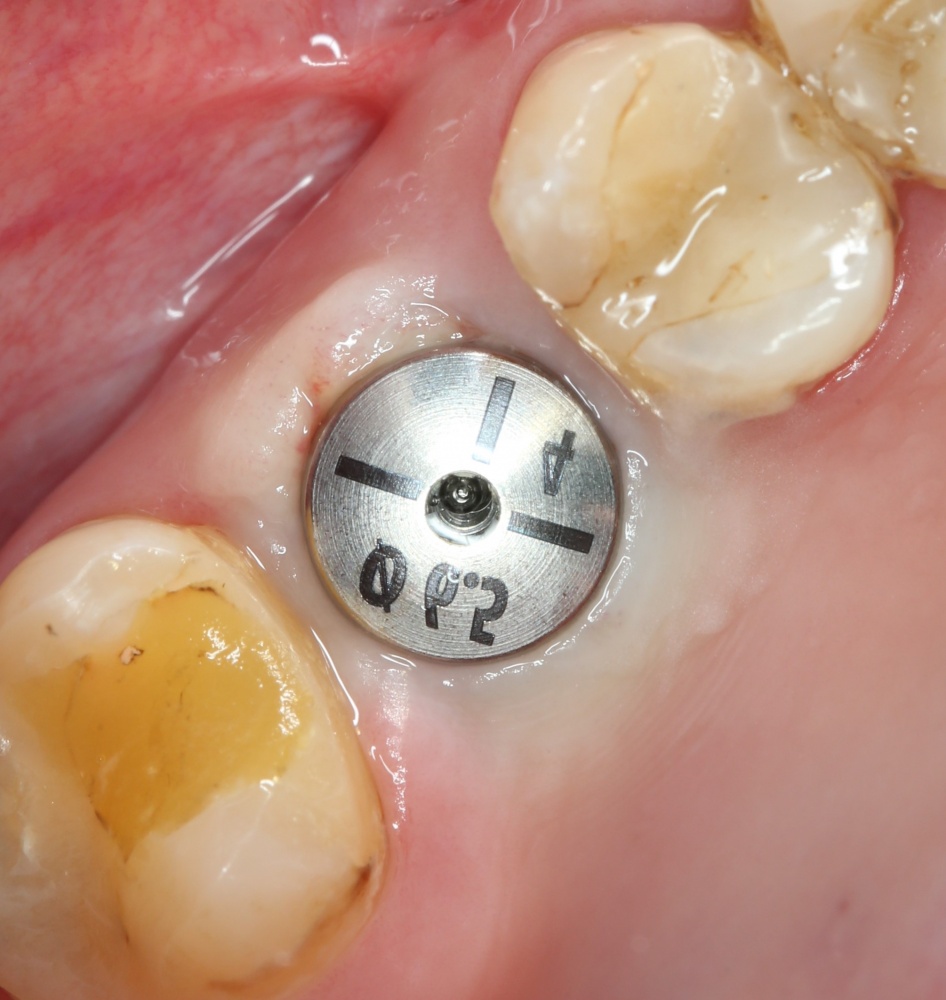

Через 3 месяца — вторая операция — установка имплантата в сформированный объем костной ткани:

Как видите. восстанавливается всё очень легко, никаких дефектов не остаётся, но при этом мы получаем важное преимущество: достаточную свободу движений при формировании субантральной полости и хороший визуальный контроль за состоянием слизистой оболочки. Никакая нажопная оптика или суперпупермикроскоп, к сожалению, не обеспечат подобный контроль при закрытом синуслифтинге. Да, операция получается травматичнее и масштабнее, чем «закрытый» синуслифтинг, но несёт в себе гораздо меньше рисков.